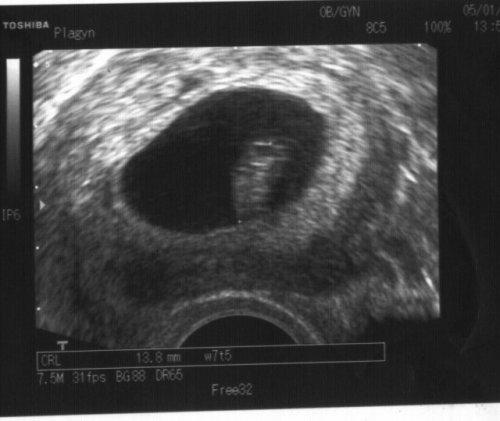

tak poslední velký ulz u mého gynekologa.. malej je zdravouckej, hlavičkou dolu a má 2,26 kg.. uf uf.. doufám, že nebudu přenášet, jinak budu rodit obříčka 🙂 ale jak já se na něj už těšííím.